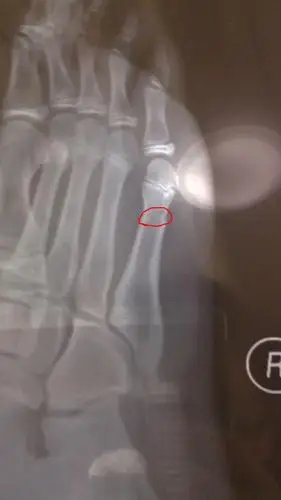

我让技术员给拍了片子,桡骨骨折!而且是典型的青枝骨折.

儿子21个月了,不小心骨折了,请医生朋友帮忙看看片子严重不?